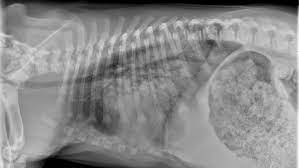

Aspiration Pneumonia In Dogs Central Toronto Veterinary Referral Clinic from ctvrc.ca A definitive diagnosis of lung cancer requires a sample of tissue (biopsy). Pneumonia is a lung infection that leads to breathing difficulties and fluid in the lungs. But in some rare cases, it may be a lung cancer (primary or secondary). My dog had pneumonia come on quickly this last august, we took her to the local er at 3am when we noticed her breathing labored and strange behavior. X rays are very helpful in the diagnosis of lung cancer in dogs. Typical signs of bacterial pneumonia include fever, difficulty breathing, lethargy and coughing. A retrospective study of 1011 hospitalized patients with pneumonia was undertaken to assess the value of routine convalescent chest radiography for detection of underlying lung cancer. The bronchioles end in the small sacs called.

A definitive diagnosis of lung cancer requires a sample of tissue (biopsy). X rays are very helpful in the diagnosis of lung cancer in dogs. Primary lung cancer are frequently located in the caudal (towards the hind end of the pet) lung lobes, however can be located in any lung lobe and are usually a single mass in the lungs, unless the tumor has spread. If your dog has a chronic cough, you'll need to rule these out. The first of these possibilities could be investigated by bronchoscopy. A definitive diagnosis of lung cancer requires a sample of tissue (biopsy). The second kind of lung cancer in dogs is called metastatic lung cancer, which means the cancer originated somewhere else in the body, but has spread to the lung. Bacterial pneumonia is an inflammation of the lung usually caused by bacterial or viral infection but can be caused by inhalation of an irritant. The respiratory system consists of the large and small airways and the lungs. Lung cancer is actually the number one killer when it comes to cancers. But in some rare cases, it may be a lung cancer (primary or secondary). In both cases, you may have. Typical signs of bacterial pneumonia include fever, difficulty breathing, lethargy and coughing.

Pneumothorax Wikipedia from upload.wikimedia.org Your exam and imaging findings will already be abnormal if you have lung cancer. The second kind of lung cancer in dogs is called metastatic lung cancer, which means the cancer originated somewhere else in the body, but has spread to the lung. Lung cancer develops due to the overgrowth of. My dog had pneumonia come on quickly this last august, we took her to the local er at 3am when we noticed her breathing labored and strange behavior. Malignant tumors trigger inflammation in surrounding normal lung tissue, and they may obstruct. Typical signs of bacterial pneumonia include fever, difficulty breathing, lethargy and coughing. A definitive diagnosis of lung cancer requires a sample of tissue (biopsy). Everybody still looks at lung cancer as a smoker's disease, but i never smoked.

Primary lung cancer are frequently located in the caudal (towards the hind end of the pet) lung lobes, however can be located in any lung lobe and are usually a single mass in the lungs, unless the tumor has spread. My dog had pneumonia come on quickly this last august, we took her to the local er at 3am when we noticed her breathing labored and strange behavior. A white spot amidst the normal black lungs can therefore be a cancer, infection. Signs of the primary tumors in dogs. I haven't touched cigarettes a day in my life. Lung cancer often misdiagnosed as pneumonia urges requests for second medical opinions. Lung cancer is actually the number one killer when it comes to cancers. A definitive diagnosis of lung cancer requires a sample of tissue (biopsy). His appetite is basically normal though his blood work shows that he is anemic. 3 doctors agree send thanks to the doctor Other common respiratory diseases that might make you worried about cancer are …. Malignant tumors trigger inflammation in surrounding normal lung tissue, and they may obstruct. Pneumonia and lung cancer both affect the lungs but one is easily treatable and the other is potentially life threatening.